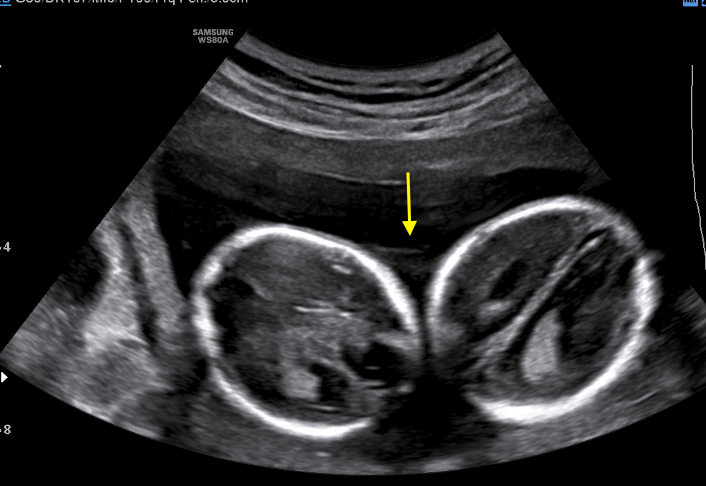

A healthy 39-year-old woman G4P3 was admitted to our high-risk pregnancy outpatient service due to a MC-DA twin pregnancy. Monochorionicity was suspected by the referring gynecologist during the dating ultrasound scan (US). The nuchal translucency US at the 12th week of gestation highlighted a “T” sign of the dividing membrane with a unique anterior placenta confirming a MC-DA twin pregnancy, as shown in Fig. 1. Soft markers for trisomy were found to be normal for both twins. The US performed during the 14th week of gestation showed the twins significantly closer to each-other standing on the same side of a free-floating thin membrane inserted on the placenta. This image raised the suspicion for a spontaneous septostomy (Fig. 2). The patient underwent amniocentesis as the combined serum screen showed an increased risk for Trisomy 21. US assisted invasive procedure did not detect the dividing membrane deposing for a PMM twin pregnancy following SS. A single sample of amniotic fluid was obtained and tested normal for fetal karyotype (46, XX). According to International Guidelines US imaging was performed every two weeks. Anomaly scan was normal and all subsequent Doppler US showed a normal twin growth and fetal wellbeing until the early third trimester [14, 15, 16]. The US performed at the 27th week of gestation showed a strict contiguity of the umbilical cords with a suspicion for cord entanglement on 3-dimensional (3D) US (Fig. 3A,B). The patient was hospitalized for close pregnancy surveillance. Fetal heart monitoring and US scan were daily performed. Steroids were administered for prevention of respiratory distress syndrome. The 29th week US scan highlighted a growth discordance ranging around 21% (symmetric growth at the 71° centile (estimated weight: 1328 gr) and at the 36° centile (estimated weight: 1043 gr) for Twin A and Twin B respectively). An episode of prolonged bradycardia was registered for Twin A. An emergency cesarean section was performed: two healthy girls were born (Twin A: weight 1360 gr, Apgar 4 and 7 at 1st and 5th minute respectively — Twin B: weight 1000 gr, Apgar 8 and 9 at 1st and 5th minute respectively). Cord entanglement was confirmed as shown in Fig. 4. The mother’s postoperative recovery was uneventful. Twins’ developmental follow-up at 12 months of age was normal.

Fig. 2.Sonogram depicting a thin free-floating membrane inserting on a unique anterior placenta with the two twins standing close to each other on the same side of the membrane.